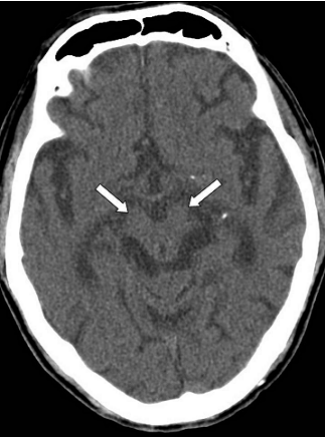

26.此電腦斷層影像中,箭號所示條紋屬於下列何種假影?

(A)motion artifacts (B)metal artifacts (C)beam-hardening artifacts (D)partial volume artifacts